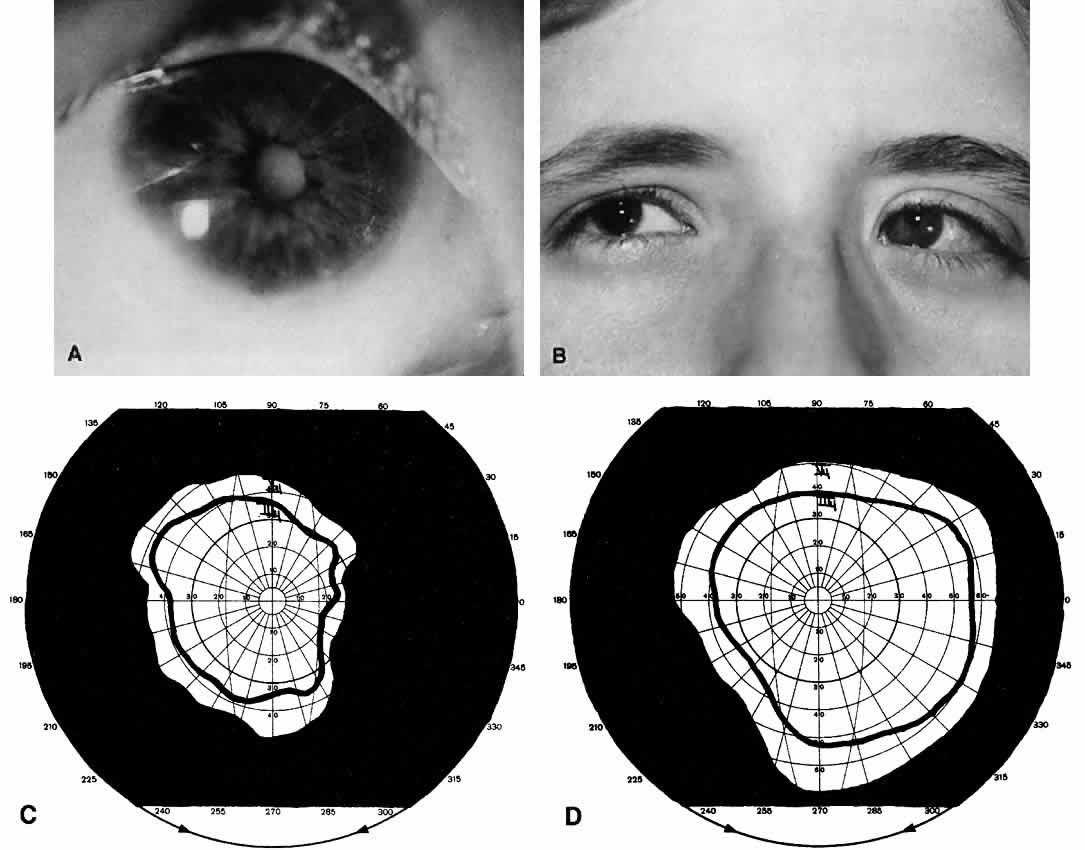

Not all cataracts require surgical treatment. Eyes with punctate or small anterior polar cataracts and others with partial opacification of the lens, such as posterior lenticonus, which only slightly interferes with the refraction of light, are best followed and not surgically treated (Fig. 1). In some cases, it is difficult to determine whether the presence of a partial cataract is responsible for a decrease in visual acuity or whether the refractive error or optical distortion produced by the cataract has produced a mild, reversible form of deprivation amblyopia. In these situations, correction of the refractive error and a trial of occlusion therapy should be attempted. If the visual acuity improves, it may be deduced that amblyopia was responsible for the loss of visual acuity and that the optical distortion produced by the partial cataract is not yet surgically significant.

Usually, anterior polar cataracts are visually insignificant and allow normal visual development (see Fig. 1). However, some affect vision, and all require careful monitoring.7 Centrally located cataracts that are on or near the posterior lens capsule have a greater effect on the refraction of light and visual acuity (Fig. 2). Nuclear cataracts associated with metabolic disorders or prenatal infections produce double refracting systems that cause optical distortion and significantly decrease visual acuity (Fig. 3).

Visual Acuity and Signs of Visual Function

Ultimately, it is the measured or estimated level of visual acuity or acuity potential that determines the need for cataract surgery. If either the measured or the estimated decrease in visual acuity produced by the cataract is sufficient to prevent adequate visual development or if signs of significantly decreased visual acuity, such as strabismus or poor central fixation, are present, cataract surgery is indicated. Use of the Teller visual acuity cards at periodic intervals can help to measure visual acuity.10 In some children, visual acuity that is below normal or decreasing can be documented accurately to support the decision to perform cataract surgery (Figs. 4 and 5). Care must be taken in interpreting Teller visual acuity data because the normal levels in young infants and children are low and span a wide range. The Teller acuity card measurement of grating visual acuity may severely underestimate the level of visual loss in patients with cataracts and amblyopia.11